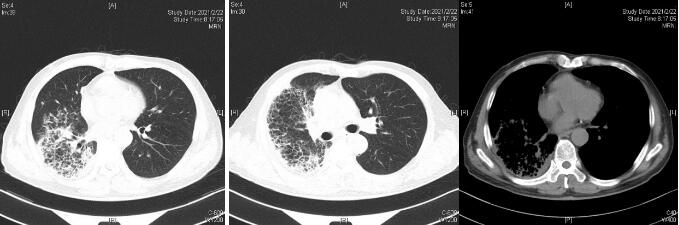

患者经过近1周治疗,临床症状较前好转,心衰纠正,炎症指标明显下降,于1月31日体温正常后转普通病房。感染方面美平降级为头孢派酮舒巴坦,继续多西环素治疗。2月2日外送标本DNA测序鉴定为Balneatrix alpica,即阿尔卑斯浴者菌。后续患者出现胸膜炎性胸痛,间断气促,复查肺部CT提示右侧胸腔积液量增多,给予穿刺引流,胸水外送经DNA鉴定报高山巴氏发菌,即Balneatrix alpica,至此患者感染的病原菌明确,考虑此菌为少见菌,对抗菌药物敏感性较高,后续抗生素方案降解为左氧氟沙星500 mg/d,经治疗3周后患者出院,后期随访追踪无不适。

| 图 4 3月23日(出院1个月后复查胸部CT平扫) |